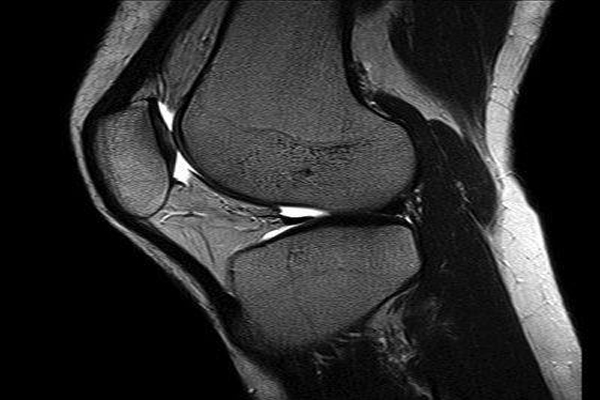

Bavi se dijagnostičkim metodama koje uz pregled, omogućavaju adekvatno postavljenje dijagnoze. Kod nas možete uraditi: RTG(rentgensko snimanje) koštanozglobnog sistema, grudnog koša, metode za snimanje organa za varenje(pasaže, irigografija), metode vizuelizacije organa za mokrenje(IVU-intravenska urografija); ULTRAZVUČNA DIJAGNOSTIKA-EHO: stomaka, karlice, color-doppler krvnih sudova, štitne žlezde, mekih tkiva. Skener(MDCT) dijagnostiku endokranijuma(galve), grudnog koša, abdomena i karlice, koštanozglobnog sistema; MR(magnetnu rezonancu jačine 1,5T) preglede glave(sa i bez krvnih sudova), kičmenog stuba, karlice, zglobova, abdomena( sa i bez žučnih puteva), dojki; MAMOGRAFIJU dojki( u sklopu prevetivnih pregleda kao i dijagnostičke mamografije i u sklopu praćenja tokak bolesti).